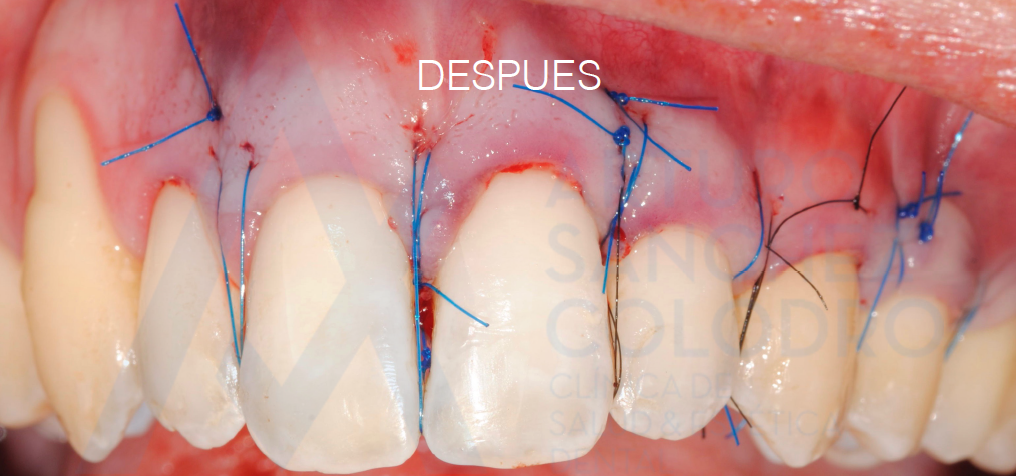

Tras la cirugía mucogingival realizada por el Dr. Arturo Sánchez Colodro en la primera parte de la boca (paciente aún en fase de tratamiento):